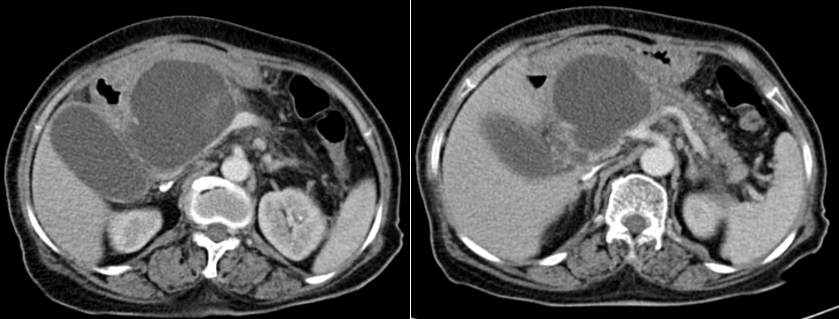

- CT Scan ngày 24/11: Viêm tụy cấp, nang đầu tụy 8x7cm chèn ép ống mật chủ gây gãn nhẹ đường mật trong gan. Được chẩn đoán: viêm tụy đợt cấp/ nang giả tụy.

Hình 1 và 2. CT scan ngày 24/11 nang đầu tụy 8x7cm chèn ép ống mật chủ gây gãn nhẹ đường mật trong gan

Hình 1 và 2.  CT scan ngày 24/11 nang đầu tụy 8x7cm chèn ép ống mật chủ

gây gãn nhẹ đường mật trong gan